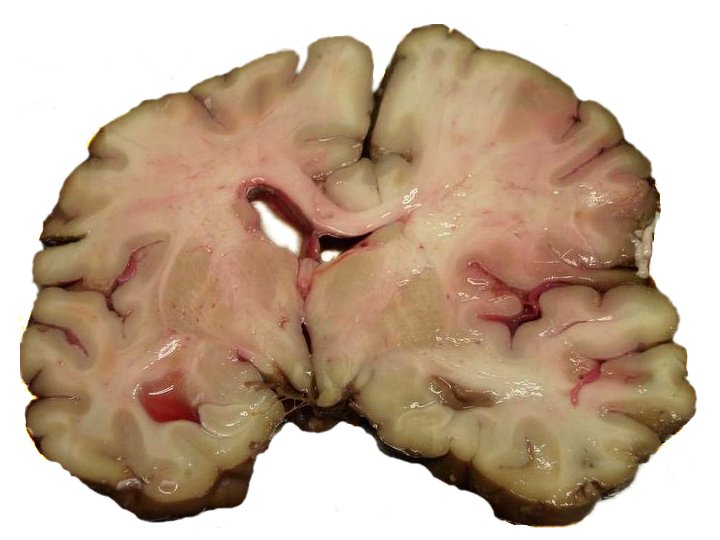

Liquefactive necrosis is the outcome of ischemic stroke.

Liquefactive necrosis results in the development of a cystic area filled with fluid that is encircled by gliosis.